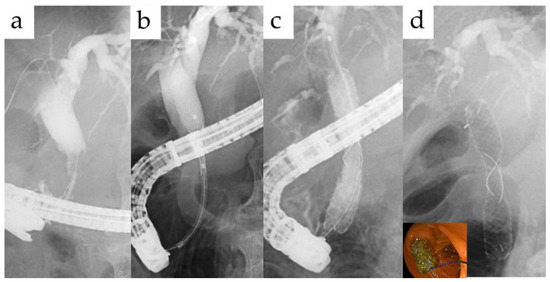

| Duodenoscopy | 20 | |

| Trans-papillary | 18 | |

| Trans-anastomotic | 2 | |

| BAE | Trans-anastomotic | 4 |

| Percutaneous | 1 | |

| EUS-guided | 1 | |